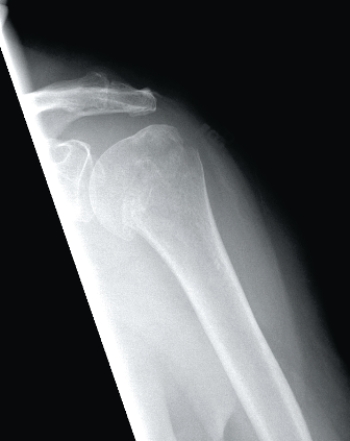

1

This image depicts a patient with:A) a Salter-Harris fracture.

B) a normal proximal humerus.

C) an anatomic neck fracture of the humerus.

D) a surgical neck fracture of the humerus.

an anatomic neck fracture of the humerus.